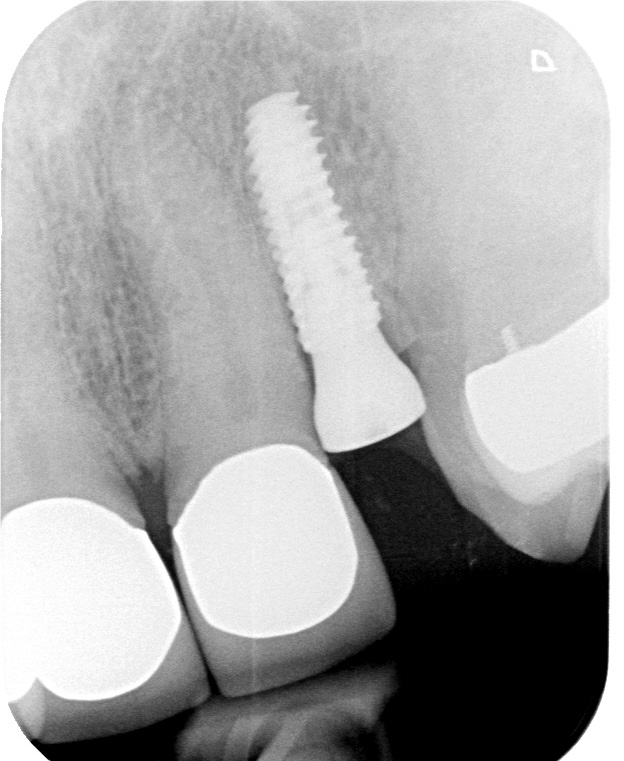

Immediate Implant Placement with Socket Shield Technique followed by

Socket Shield (SS) Technique for Bone Preservation in Anterior Implants Implant Socket Shield Technique the socket shield technique can be used in dental implant treatment, but it remains difficult to predict the long. the primary objective of this systematic review was to answer two fundamental questions: the aim of this review is to present the currently available studies on the treatment outcome of socket shield technique (sst). the socket shield. Implant Socket Shield Technique.